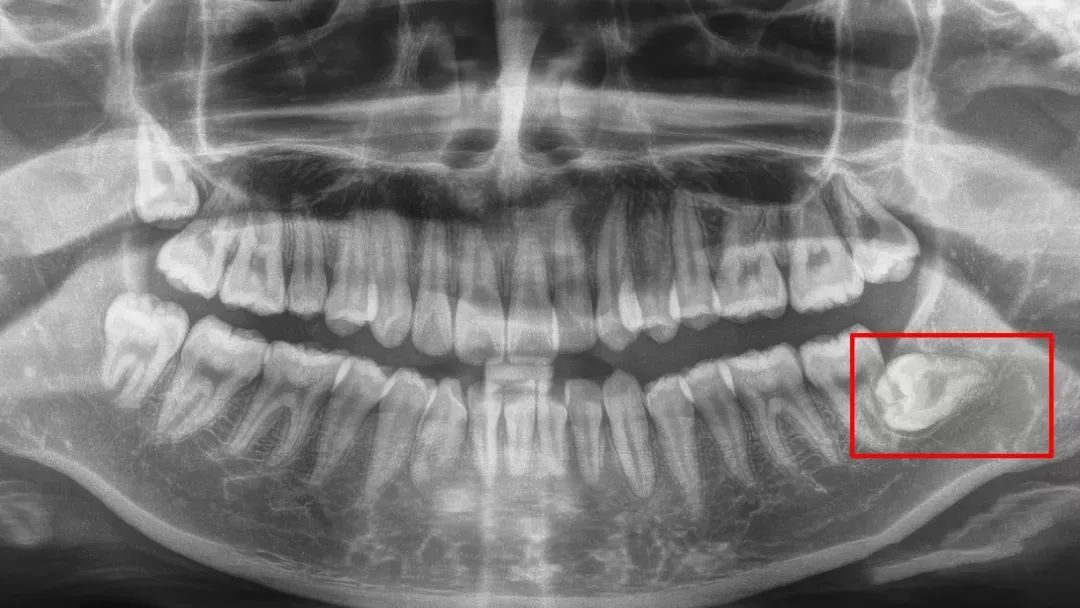

▲多生牙、缺骨。

▲七号牙近中生长 + 阻生智齿。